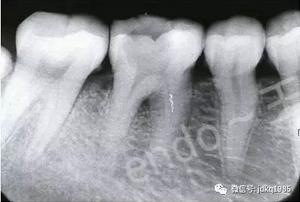

臨床病例報(bào)告:患者為30歲女性,因后牙自發(fā)性疼痛于當(dāng)?shù)蒯t(yī)院行“根管治療”,治療過程中出現(xiàn)“斷針”,建議轉(zhuǎn)診,遂來我院就診。X線檢查可見46近中根管中上段約3mm的高密度影像,其余根管內(nèi)未見充填影像,根尖區(qū)見密度減低透射影。由于患者存在根尖病變,且分離器械位于根管中上段,因此我們給患者擬定了根管內(nèi)分離器械取出的治療方案。

術(shù)前X線片可見近中根管內(nèi)分離器械